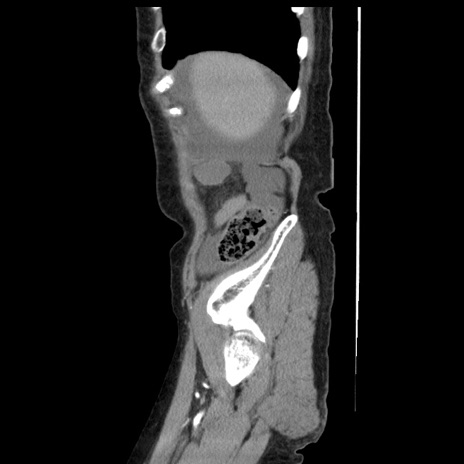

症例1(矢状断像)

【症例】80歳代女性

【主訴】腹痛

【現病歴】8時間前から腹痛あり来院。

【既往歴】糖尿病、脂質異常症、子宮体癌にて子宮全摘術

【身体所見】意識清明・会話良好だが腹痛で苦悶様、全腹部にわたって反跳痛と圧痛あり

【データ】WBC 13600、CRP 0.14、LDH 224、CK 90